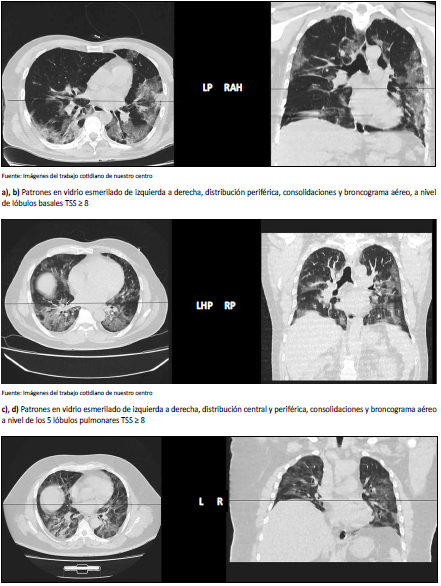

Los patrones tomográficos en vidrio esmerilado característicos, se aprecian en la figura 1.

Un Score TSS ≥ 8 en pacientes con neumonía COVID-19 en su admisión hospitalaria puede ser considerado predictor de admisión a UCI (23). Se ha descrito que el score TSS como predictor de mortalidad. [23-26] La presencia de un patrón de crazy paving(CP) y de consolidación estuvieron asociados a la admisión a UCI. Patológicamente, puede representar un continuo de aumento del daño alveolar de mínimo, representado por GGO a difuso o diseminado, representado por consolidaciones extensas.[27] Datos importantes como la presencia o ausencia de comorbilidades respiratorias o cardíacas (o ambas) subyacentes, en la población de estudio no se conocía al detalle esperado. Uno podría sostener que algunas de las diferencias observadas entre los pacientes graves y las formas leves de la enfermedad podrían deberse en parte a comorbilidades respiratorias o cardíacas. Por ejemplo, GGO, el engrosamiento del tabique interlobulillar y el derrame pleural podrían ser debido a una enfermedad cardíaca subyacente o sobrecarga de líquidos en lugar que el daño pulmonar directo causado por el virus. Los estudios controlados pueden ayudar a diferenciar el daño directo al pulmón como efectos de la infección de los causados por las comorbilidades subyacentes. [28] Otro de los aspectos evaluados fue la presencia del signo de engrosamiento vascular(EV), este signo de vaso agrandado o engrosado observado en la neumonía COVID-19 usando TCT sin contraste, puede representar una correlación de imágenes de cambios vasculares histopatológicos distintivos, informados en estudios de autopsias [29], en el presente estudio se describió la presencia de este signo en ambos grupos de pacientes, sin embargo, no se encontró diferencia significativa; a pesar de ello consideramos que se debe evaluar este signo en series de pacientes más grandes, dada su importancia fisiopatológica, a la luz de los estudios histopatológicos a nivel pulmonar y su probable correlación con endotelitis y trombosis.[30] Es destacable que en la presente serie sólo hubo 01 fallecido con 26 días de hospitalización en UCI, en el período de tiempo descrito.